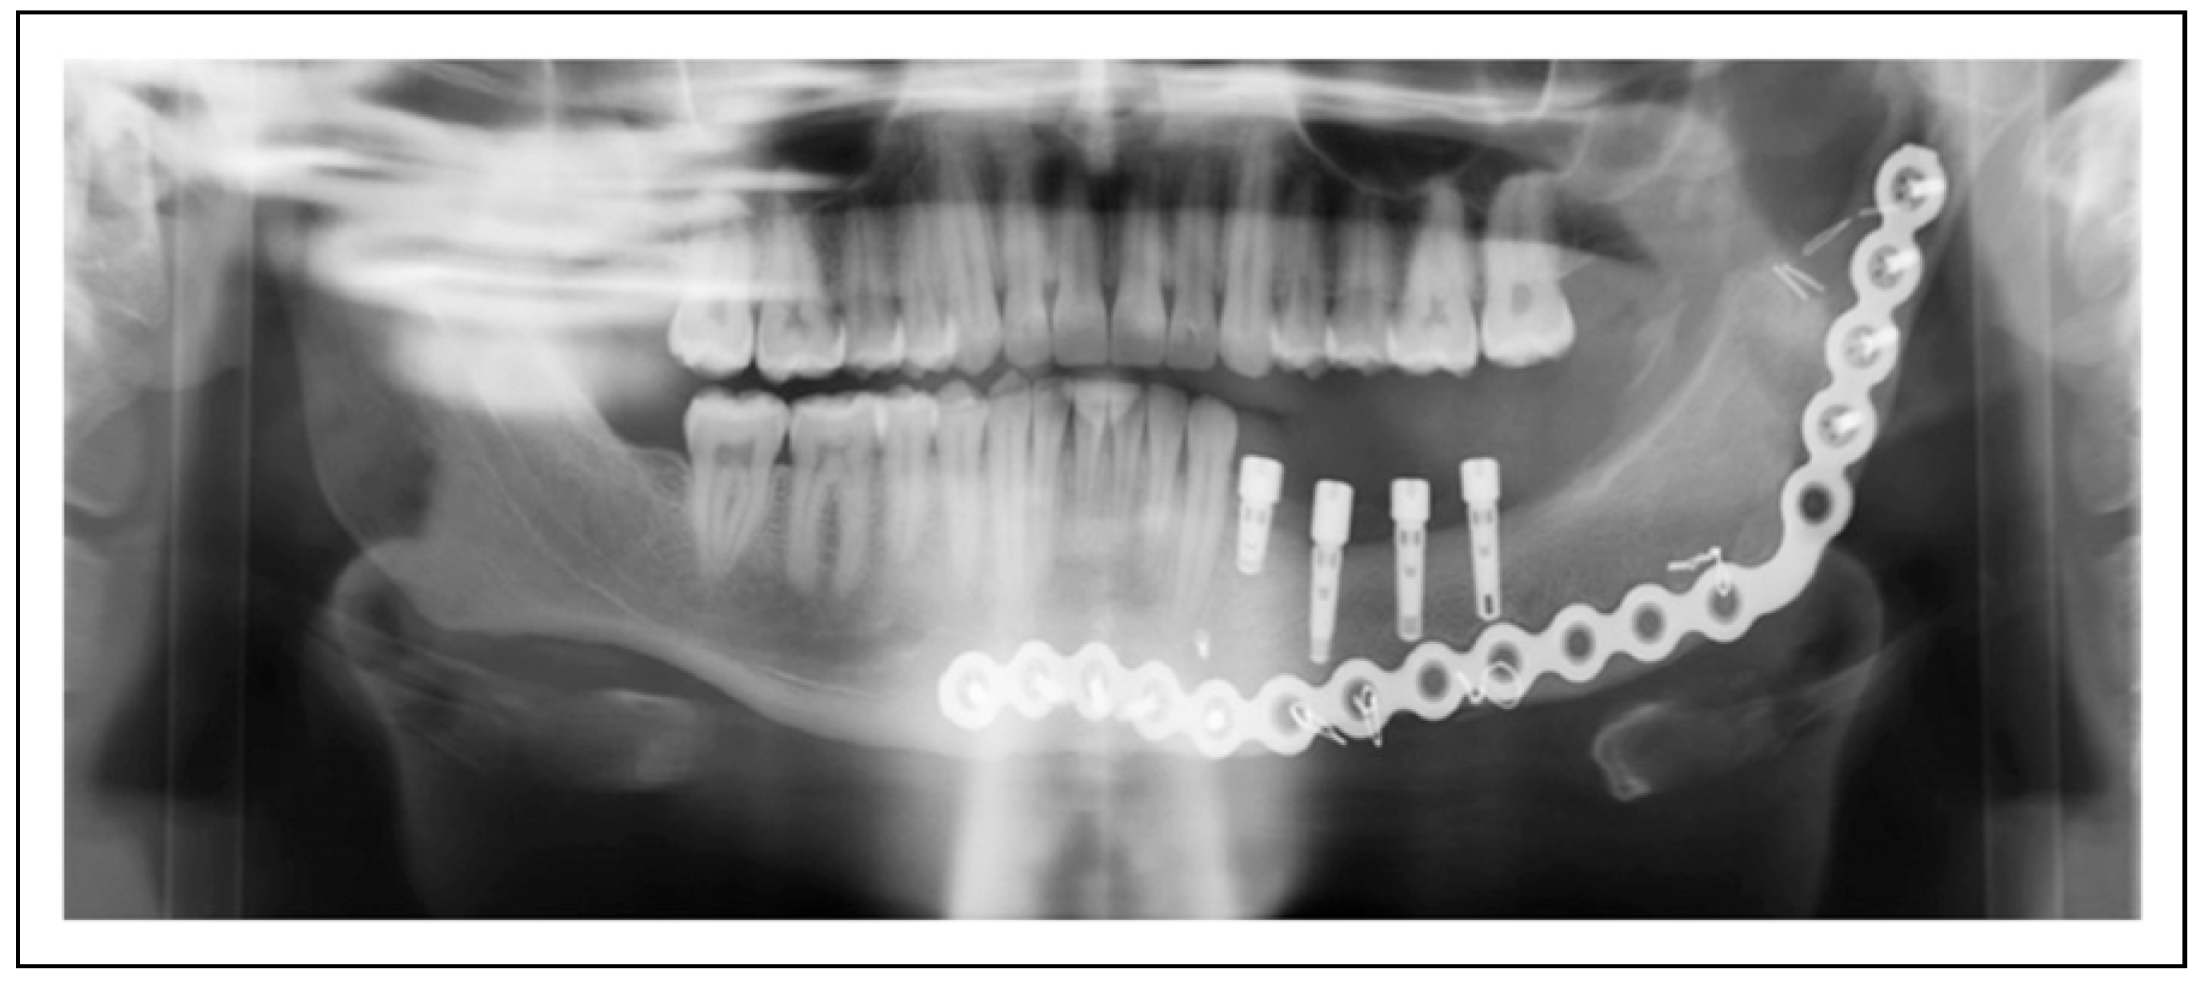

Figure 1.

Patient 2 is restored with 4 mandibular implants status post resection and reconstruction using tissue engineering techniques. These implants are without radiolucency or other signs of pathology 8 months post-operatively.